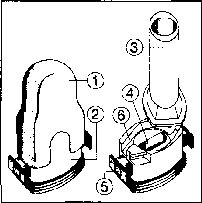

İnhalasyon cihazı aşağıdaki bölümlerden oluşmaktadır:

1. Ağızlığı koruyan bir kapak

2. İlacın kapsülden düzgün olarak salınmasını sağlayan bir taban.

Taban kısmı aşağıdaki kısımlardan oluşur.

3. Ağızlık

4. Kapsül bölmesi

5. Kapsül bölmesinin iki yanında basıldığında çıkan iğneler aracılığıyla kapsülleri delmeye yarayan düğmeler (“kul akç ıklan”)

6. Hava geçiş kanalı_